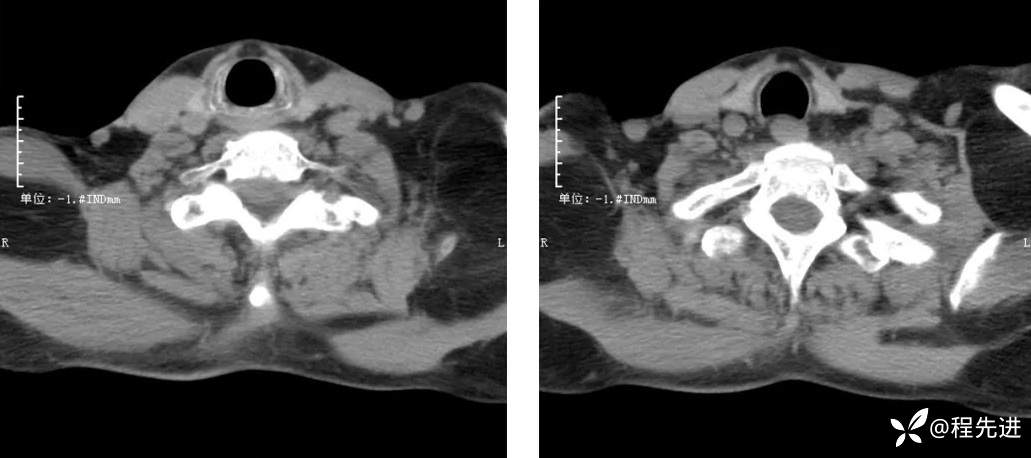

CT检查: